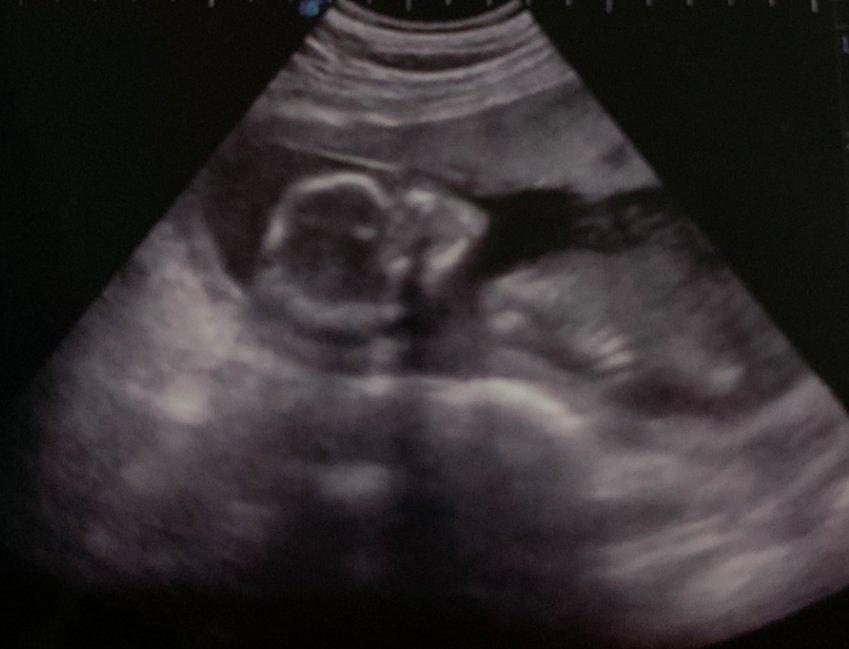

Infertilidad de origen desconocido. 5 ias.1 fiv.2 transf. 2015 nace mi primera hija . 2017 aborto. 2020 tercera transfe y nace mi segundo hijo.